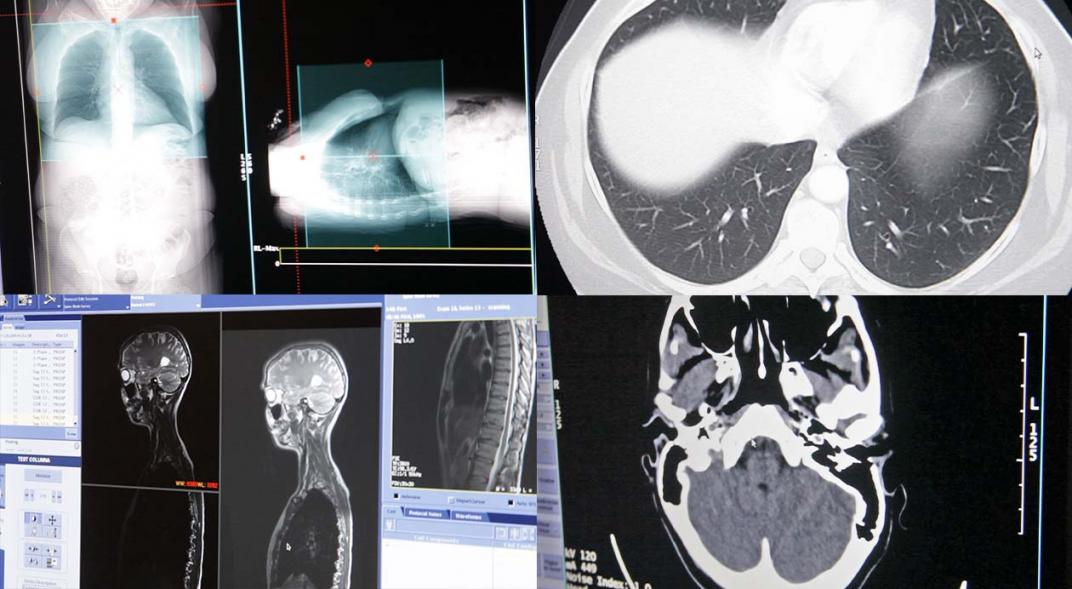

El nuevo tomógrafo permite explorar diferentes partes del cuerpo para evaluar y diagnosticar enfermedades de los huesos, hemorragias, enfermedades cardíacas, toda la patología encefálica, torácica, abdominal y tumores. Este equipo crea imágenes transversales del organismo e integra una técnica de “Revolution HD” que reduce las imágenes borrosas producto del movimiento, tanto de los órganos (corazón, por ejemplo) como los involuntarios del paciente. Este sistema, sumado a la tecnología espectral, logra ver con mayor claridad las arterias coronarias, el contraste entre los tejidos y la composición química de las sustancias que forman parte del organismo (el calcio, el agua y la sangre) y de algunas patologías.

El estudio consiste en captar imágenes del cuerpo a partir de una dosis de radiación determinada  que se origina en el tubo de rayos X del Tomógrafo. Este procedimiento no genera dolor y la dosificación de Rayos X se ajusta automáticamente dependiendo del tamaño del paciente, de la localización anatómica y de la patología que se debe investigar. Mediante este tipo de tomógrafos es posible, entonces, regular la dosis de radiación a tasas bajas para disminuir riesgos en los pacientes.

Otro aparato que incorporó el Servicio de Diagnóstico por Imágenes es un resonador. Las características de este equipo consisten en un tubo cerrado donde ingresa la camilla en su totalidad para realizar el examen y para centrar la zona que se debe estudiar. Con la ventaja de un diseño de 70 cm de diámetro de amplitud del tubo y  una camilla que resulta ser más ancha, confortable y en posición baja, permite al paciente una mejor tolerancia al estudio y evitar el rechazo por claustrofobia, dado el mayor tamaño del sitio para realizar el examen.

El nuevo resonador, con un sistema Signa Pioneer, reduce los niveles de decibeles de sonido, brindándole al paciente un estudio cómodo y sin ruido. Además, manteniendo una respiración libre y fluida, este sistema posibilita corregir los movimientos, permitiendo adquirir imágenes del cuerpo sin necesidad de sostener la respiración en muchos casos.